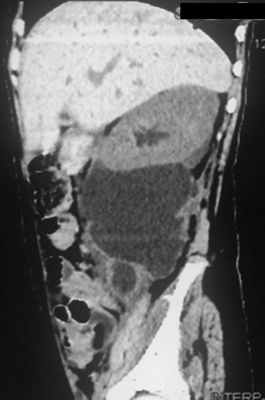

Пациентка Ш., 8 лет, пострадала в дорожно-транспортном происшествии в апреле 2018 г., оказавшись пассажиром автомобиля в момент его столкновения с препятствием на высокой скорости. Взрослый пассажир, также находившийся в машине, погиб, девочку доставили в больницу, расположенную в одном из городов Южного федерального округа Р.Ф. Состояние ребенка характеризовалось как тяжелое, но показаний к немедленному хирургическому вмешательству не выявлено. В течение 15 дней состояние оставалось относительно стабильным, за это время проведено рентгенологическое обследование, в ходе которого установлено наличие множественных скелетных травм (переломы костей таза, верхних и нижних конечностей). К концу этого периода при повторном УЗИ выявлены признаки ранее не распознанного повреждения правой почки с формированием обширной околопочечной урогематомы. МСКТ с контрастным усилением показала снижение экскреторной функции правой почки с экстравазацией контрастного препарата и распространением его до уровня крыла подвздошной кости (рис. 1). Рис. 1. Обширная урогематома у пациентки Ш. через 17 сут после травмы.